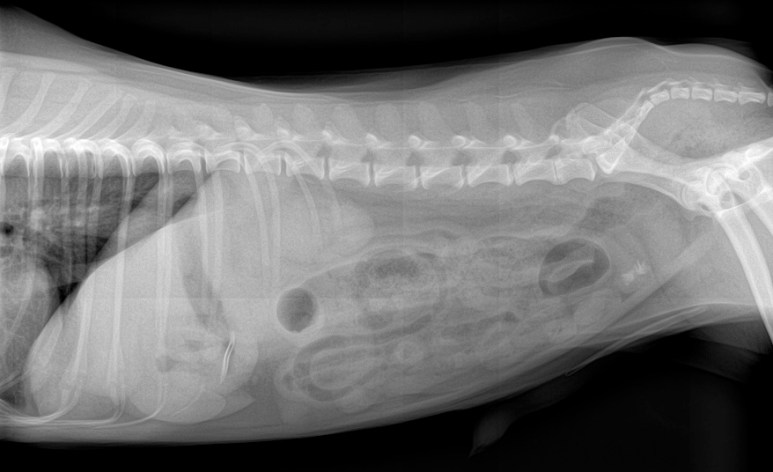

Étant donné que le chien démontrait toujours des signes d’obstruction intestinale, il est allé en laparotomie afin de retirer ce mystérieux corps étranger. On voit sur les radiographies post-op que le corps étranger a bien été retiré.